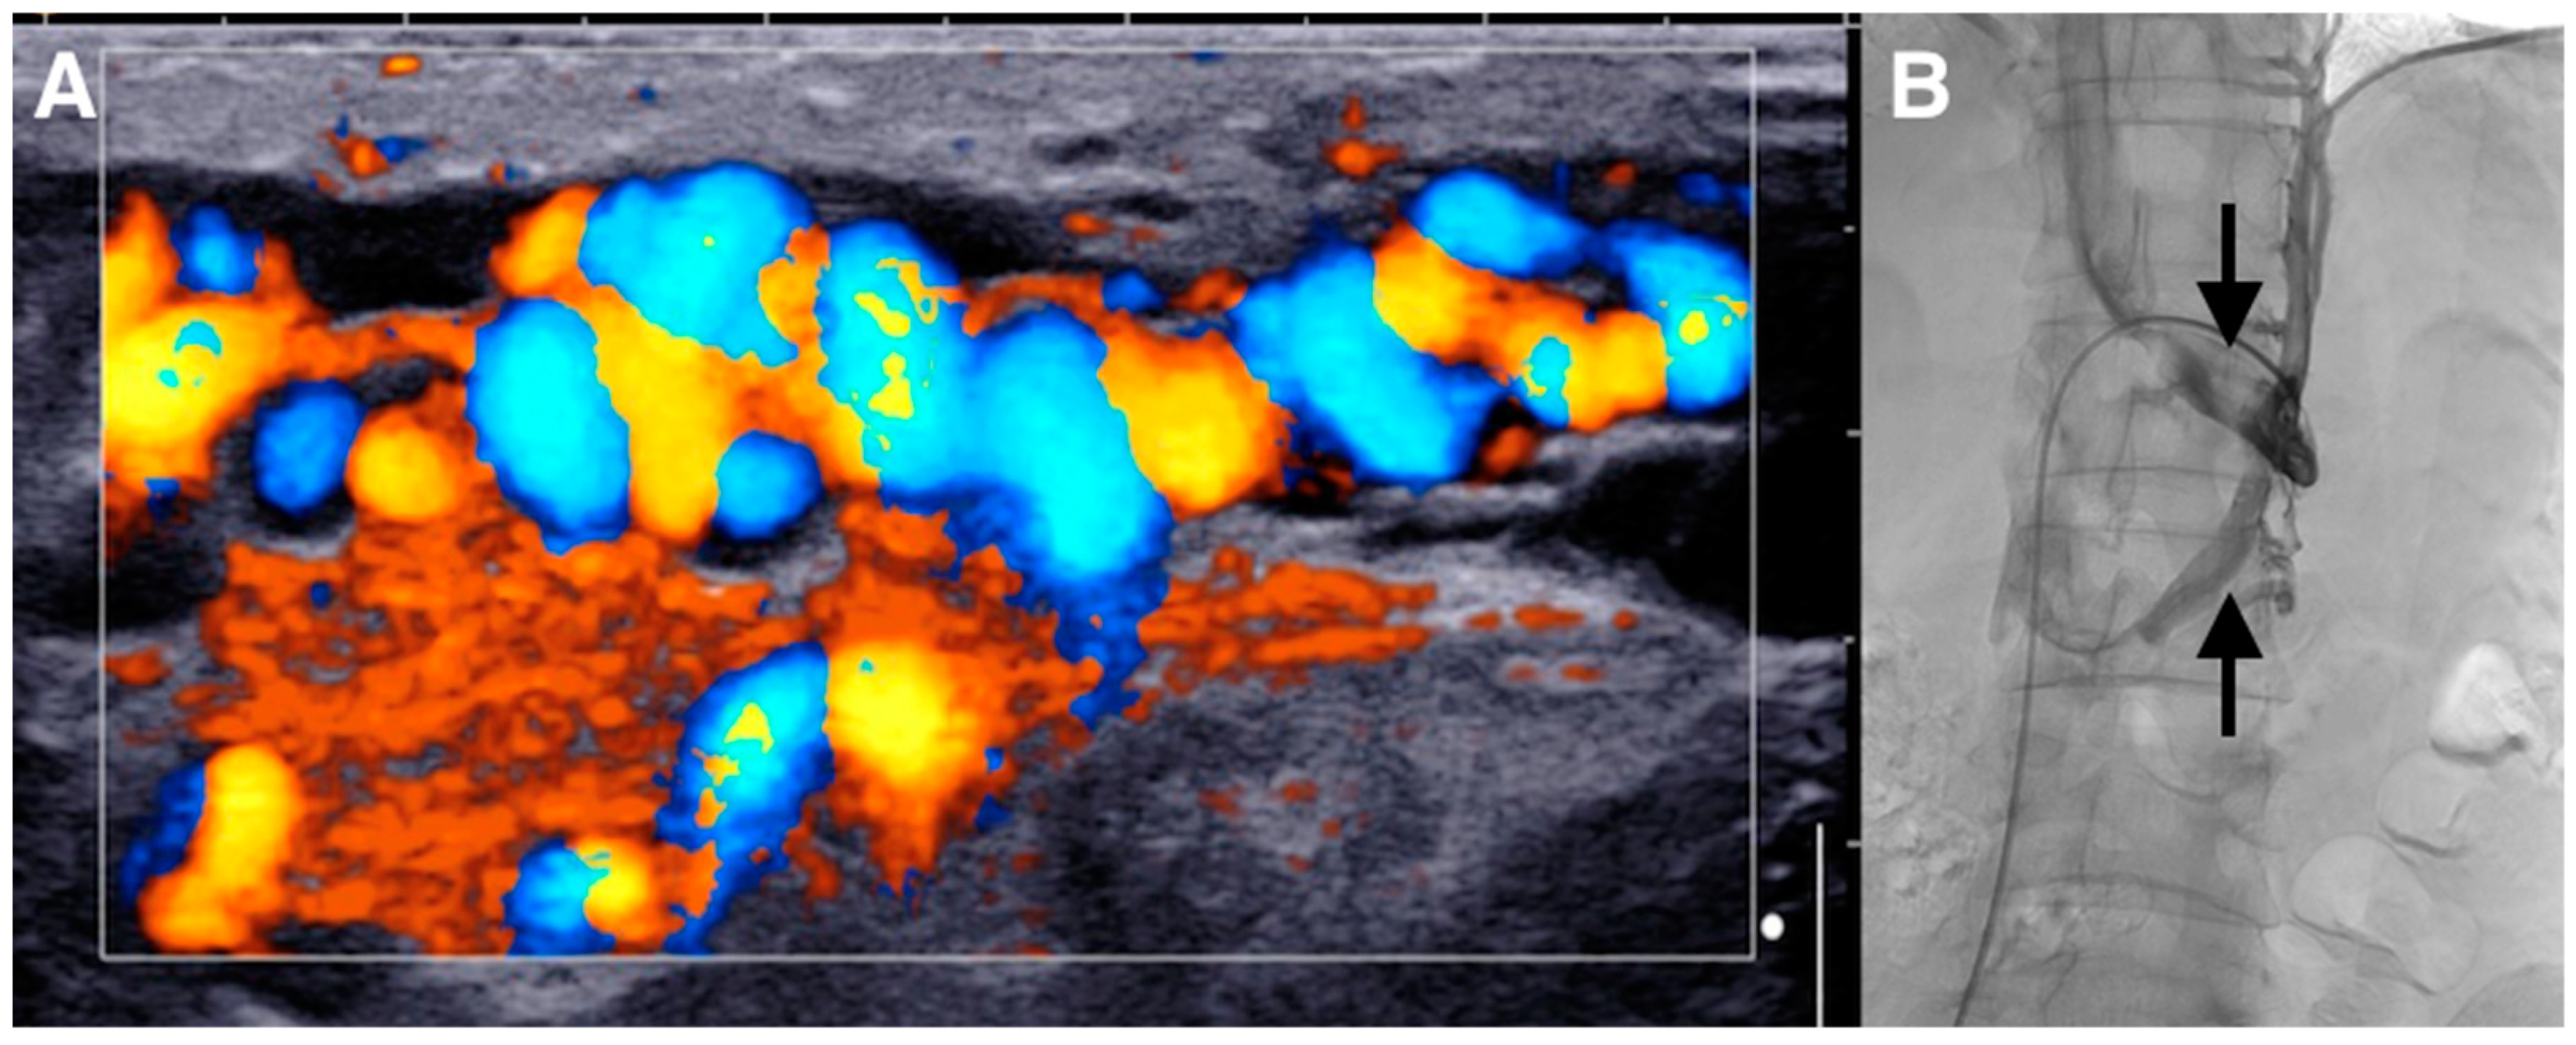

Figure 1. Varicocele repair is mainly indicated in young adult patients with clinical palpable varicocele and abnormal semen parameters or pain. Indeed, evidence from the literature demonstrates that varicocele treatment is associated with a significant improvement in sperm features and pregnancy rate compared to observation [1,2]. Many surgical techniques have been described for varicocele treatment. In recent decades, laparoscopic ligation, microsurgical varicocelectomy, percutaneous retrograde sclerotherapy or embolization, and antegrade scrotal sclerotherapy were the main alternatives to standard inguinal or suprainguinal surgical ligation. None of the previous techniques showed to be superior to the others in terms of success and complication rates. Only in recent years, microsurgical repair and sclero-embolization methods seem to be more effective than inguinal and suprainguinal ligation in terms of recurrence rate. Embolization has the advantage of being a minimally invasive procedure, performed under local anesthesia, with low cost and low risk. The most used approach is the retrograde endovascular approach, mainly with coils. However, nowadays an interventional radiologist’s preference is still the most relevant criteria to choose the approach and the embolic material for varicocele treatment [3,4]. In this case, we describe the use of glue by antegrade approach for varicocele embolization. We also describe our step-by-step technique. (A) The patient was a 29-year-old male who presented with a painful left-sided varicocele. Doppler ultrasound demonstrated a large left varicocele. Ultrasonographic criteria were usual for varicocele diagnosis: varicocele venous pampiniform plexus diameter > 3 mm and the retrograde flow into the plexus under Valsalva maneuver as shown here on color Doppler image [1]. (B) He was referred to interventional radiology for endovascular embolization. Standard retrograde embolization via the left renal vein by transfemoral approach was not possible, because there was a left circum-aortic renal vein making the visualization and catheterization of the testicular vein impossible (arrows).